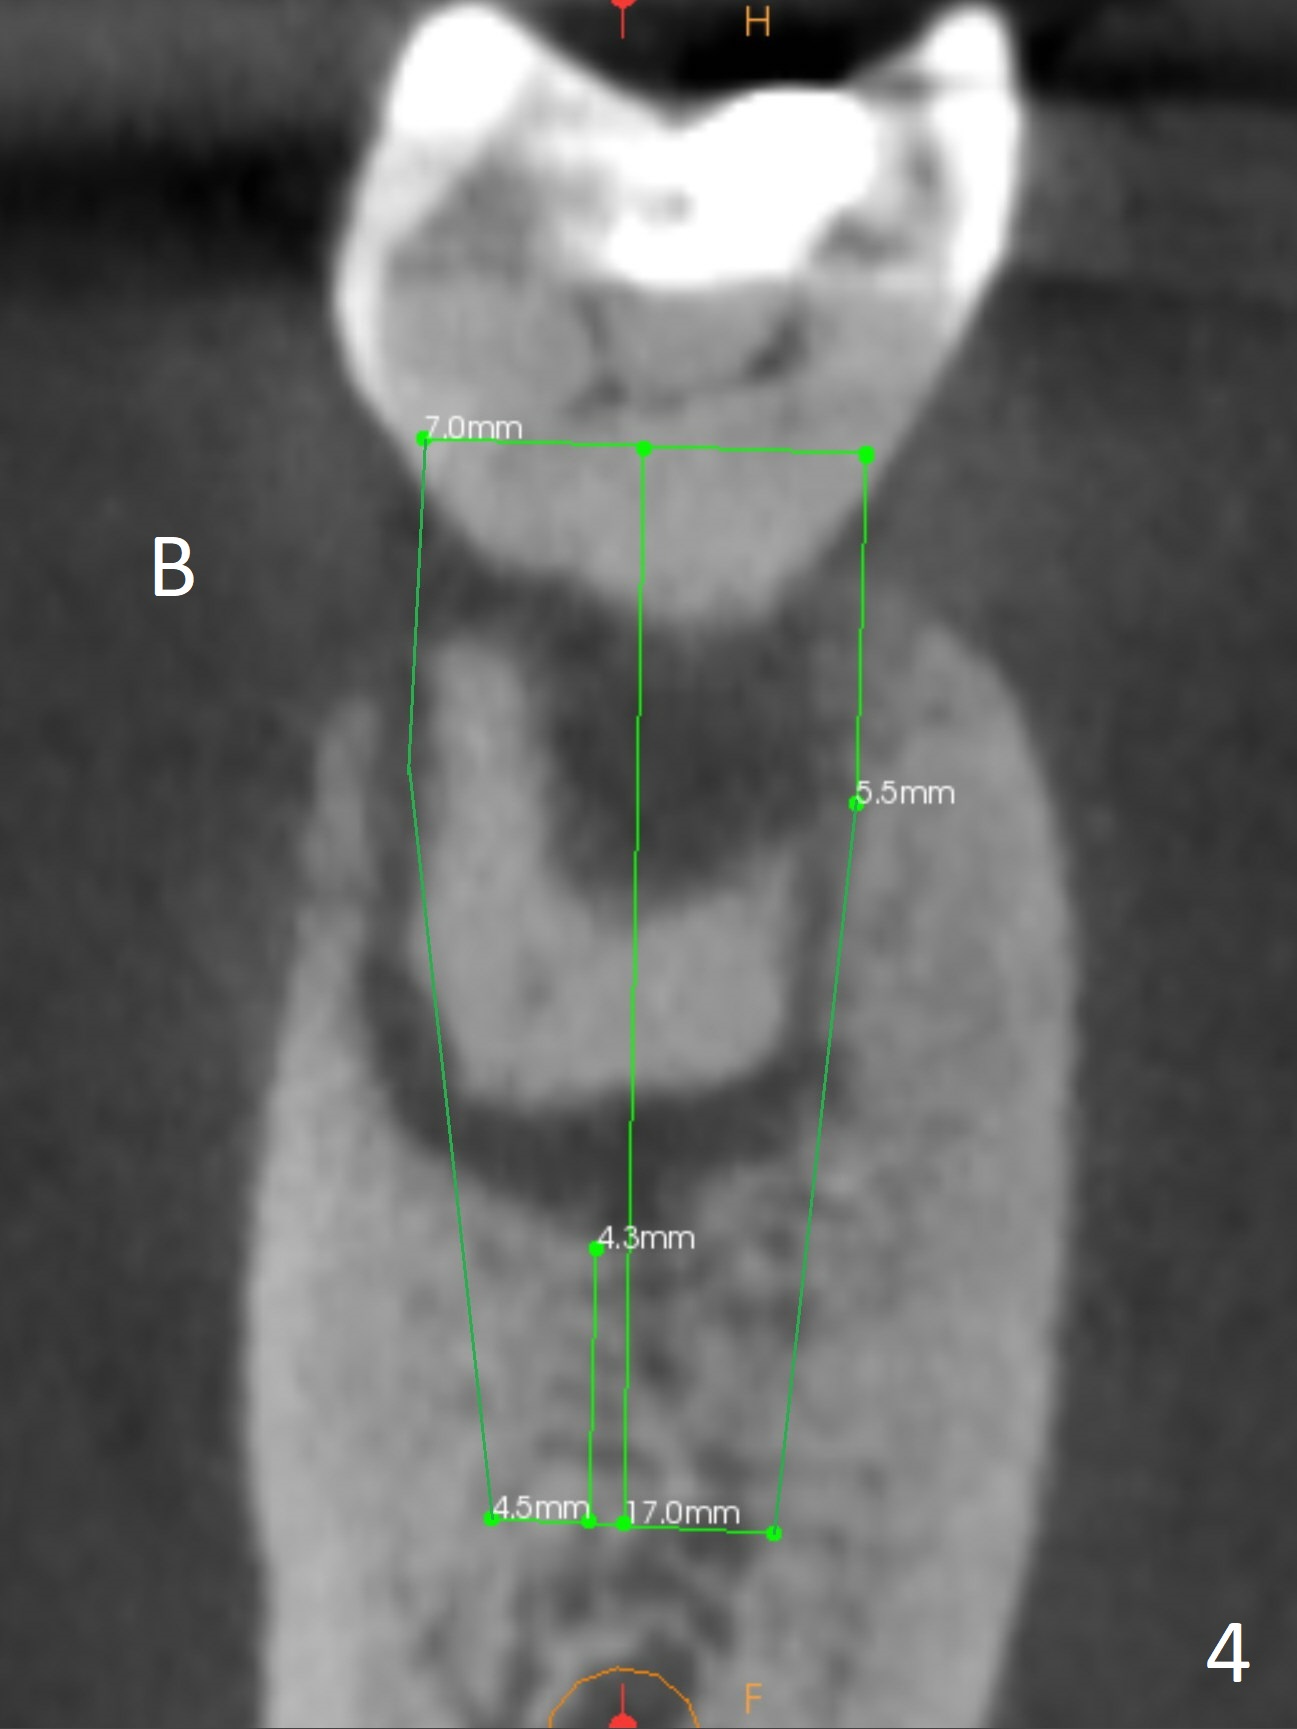

A 71-year-old woman (bruxer) wants to remove the tooth #30 (occlusal trauma, possible root fracture) for implant following the one at #14 (Fig.1). IBS abutment screw tends to loosen in functioning if the implant is placed too deep and/or off the longitudinal axis. If these two conditions are not controlled well, switch to a large tissue-level implant. A drawback of placing the implant in the septum is that the mesial margin of the abutment (Fig.2 pink) is subcrestal. If the implant is placed in the mesial socket (Fig.5 red line), the imagined abutment margin plane (white line) is parallel to the mesiodistal crests. Initial osteotomy entry point in the mesial socket and trajectory should be adjusted intraop (compare Fig.6 and 7) so that the apex of the implant will not be too close to the apex of the tooth #29 (to avoid truncating the neurovascular supply to the tooth (Fig.6 red arrowheads)) at the same time the abutment inclination is not too compromised (Fig.7). To prevent pressure upon the buccal (Fig.4 B) plate, osteotomy should be slightly lingual and/or the diameter of the implant is to be < 7 mm. Use a 3 mm unipost for provisional and probably 5 mm one for definitive restoration. Apply bonding to the post if the implant is 6 mm or less. The provisional margin should be wide and deep for deep margin and easy impression later. Use IS drills with 4 mm stopper for osteotomy if the septum is absent. Prepare Rongeur and surgical handpiece to remove the remaining septum if needed. Be wary of the distally curved root tip of #29. In fact there is a mesiodistal crack line (Fig.8 arrowheads) with buccal recession (Fig.9, 2 weeks preop).